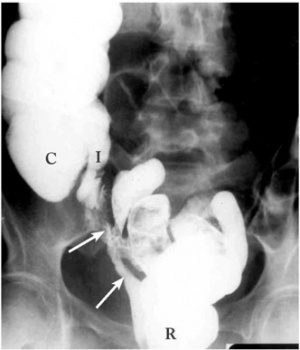

נצור חלחולת-נרתיק בחלקו התחתון של הנרתיק אפשר לרוב למשש ולאבחן בבדיקה חלחולתית ובאמצעות אנוסקופ או מראה נרתיקית. לעתים נמצאים שרידי צואה בתוך הנרתיק, המעורבים בדרך כלל בתהליך דלקתי פעיל. במקרים שבהם אין רואים בוודאות את פתח הנצור, אפשר לאבחנו על-ידי החדרת חומר צבע לחלחולת, שמופיע לאחר כ- 20-15 דקות על גבי סתם נרתיקי. השלמת הבירור מחייבת תמיד ביצוע רקטוסקופיה (תצפית חלחולת), חוקן בריום (תצלום 17.8), צילומי מעי דק, ולעתים גם צילום כליות (Pyelography) , צילום נרתיק (Vaginogram) וצילום הנצור. כל ממצא חשוד באזור שבקרבת הנצור מחייב ביופסיה לאבחנת תהליכים דלקתיים או ממאירים.